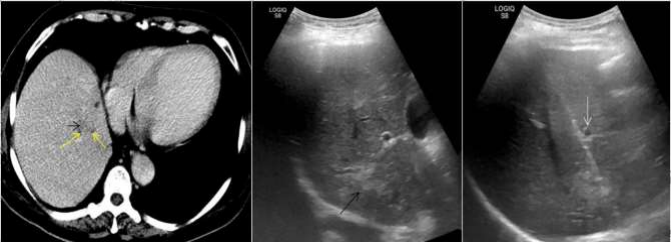

Figure 02: In this treated case of carcinoma rectum, surveillance CT scan reveals a 13 mm nodule in segment VII of liver (yellow arrow in a). USG guided FNAC was performed from this small liver lesion (as shown in b, yellow arrows). Entire course of the 15 cms 23G chiba needle (white arrows) is seen when the needle is parallel to the transducer. Tip of the needle is seen in mildly hyperechoic liver lesion in segment VIII (yellow arrows). Blue arrow shows hepatic vein. Cytology report suggestive of metastasis.

Figure 05: 42Y/Female, known case of carcinoma breast with new onset 5 mm lesion in segment VIII of liver. Note the location of the lesion beneath the rib. Needle was inserted in this small lesion in breathhold during inspiration. White arrow denotes rib, red arrows denote the liver lesion and yellow arrow denotes the spinal needle with its tip inside the liver lesion. Background liver shows fatty infiltration. Cytology report suggestive of reactive atypia in the liver lesion.